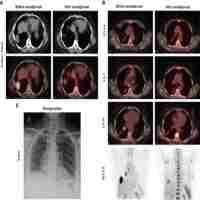

| Abstract | Objective The present study endeavors to furnish an exhaustive review of the research advancements on solid tumors harboring RET rearrangement within the Chinese context, particularly emphasizing the examination of real-world therapeutic strategies and clinical outcomes observed in individuals diagnosed with advanced non-small cell lung cancer (NSCLC). The review delves into a critical assessment of the therapeutic efficacy of targeted RET inhibitors, while also scrutinizing the diverse array of treatment modalities employed in the Chinese patient population. Methods The study conducted a comprehensive review of the advancements made by Chinese scholars in the realm of RET driver genes. It delved into the analysis of the incidence of RET rearrangements in solid tumors, alongside an examination of the varied treatment paradigms and their current status within China. Utilizing the RECIST 1.1 criteria, the study evaluated the therapeutic efficacy achieved in RET-positive NSCLC patients undergoing diverse treatment modalities. Furthermore, treatment-related adverse events (TRAEs) were meticulously graded following the Common Terminology Criteria for Adverse Events (CTCAE). Results A retrospective, multi-center, real-world analysis was conducted, encompassing 64 patients diagnosed with pathologically confirmed RET rearrangement advanced non-small cell lung cancer (NSCLC) between December 2015 and November 2023. Notably, KIF5B-RET emerged as the most prevalent RET fusion partner, accounting for 59.4% of cases. Therapeutic interventions among these patients included specific targeted inhibitors such as Pralsetinib (48.4%), chemotherapy (34.3%), multi-target inhibitors (15.6%), and one case (1.6%) involving immunotherapy combined with anti-angiogenic therapy. In terms of progression-free survival (PFS), Pralsetinib monotherapy demonstrated a median PFS of 16.03 months, outperforming chemotherapy (2.87 months; p < 0.0001), chemotherapy combined with anti-angiogenic therapy (6.90 months; p = 0.048), and multi-target inhibitors (2.50 months; p < 0.0001). Furthermore, the one-year and two-year overall survival (OS) rates for Pralsetinib monotherapy were 64.3% and 46.4%, respectively. Regarding safety, 71.0% of patients receiving Pralsetinib experienced at least one adverse event, with 45.2% classified as grade 3–4 in severity. Notably, no fatalities were attributed to adverse events. Common adverse events included hemoglobin reduction (35.5%) and neutropenia (32.3%), indicative of an overall favorable safety profile for Pralsetinib in this patient population. Conclusion This study encapsulates the research endeavors and treatment advancements of RET rearrangement solid tumors within the Chinese healthcare landscape, specifically highlighting the diverse real-world therapeutic approaches and their effectiveness in managing advanced RET rearrangement NSCLC among Chinese patients. Notably, targeted RET inhibitors like Pralsetinib have emerged as potent therapeutic agents, exhibiting remarkable efficacy and a manageable safety profile in this patient cohort. These findings underscore the potential of Pralsetinib and similar targeted therapies as novel treatment options for individuals with RET fusion-positive NSCLC. |